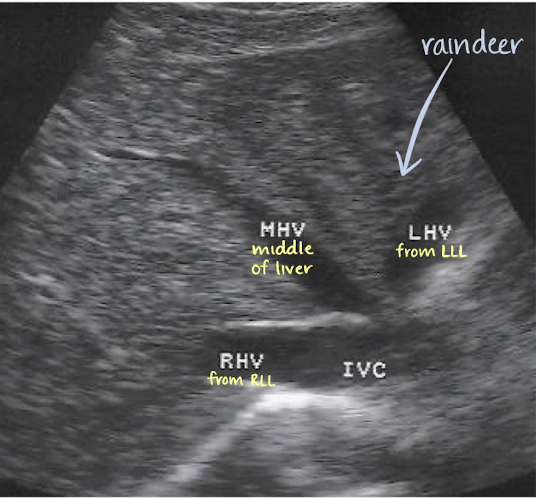

hepatic veins (HVs)

largest visceral tributaries of IVC

courses from inferior aspect of liver to superior aspect

3 HVs: left, middle, and right hepatic veins

drains liver posteriorly into IVC

thickens as it gets closer to IVC

“reindeer” or “playboy bunny” sign

LHV, MHV, and RHV